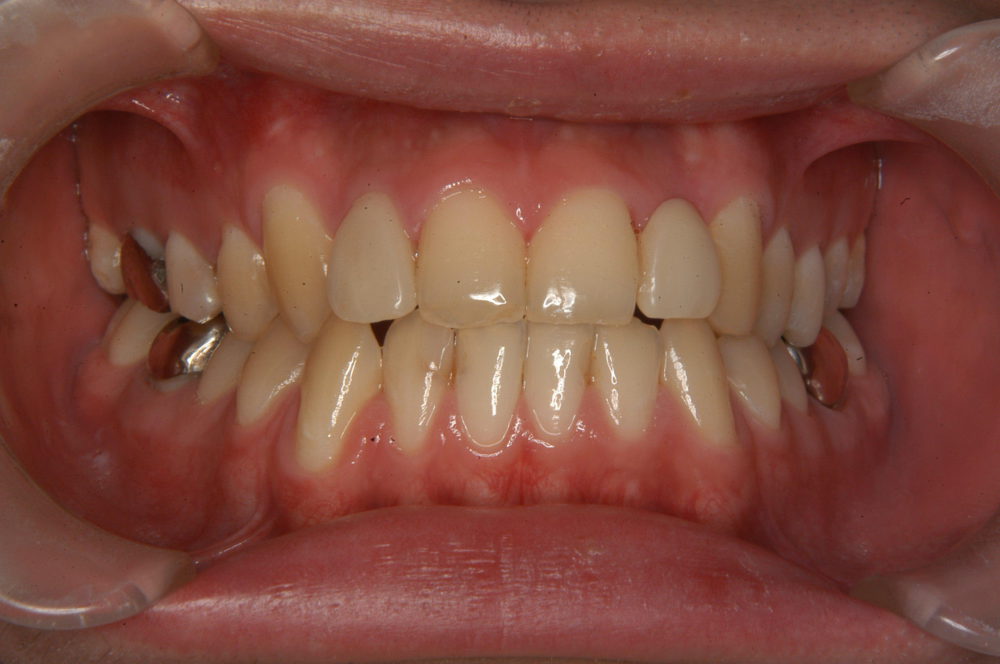

上顎前歯の審美修復のための部分矯正

上顎の右側2番目の歯が矮小歯と呼ばれる小さな歯が審美的にも機能的にも改善が必要な状態です。また、左側は2番目の歯が欠損している状態です。これらを改善するためには右側2番目の歯の形をセラミッククラウンで修復し、左側には欠損した2番目の歯を作る必要があります。修復治療が可能にするために、部分矯正を行いました。

Before

After

前歯に金具を装着後、2番目の歯に修復を施すために歯を移動させてスペースを作る方針を立案しました。

上顎前歯に金具を装着し、約8ヶ月で装置を外し、仮歯にて修復し経過を観察します。歯列の安定を確認した後に最終的な修復物(セラミッククラウンなど)を装着します。

主訴

上顎前歯の審美改善

診断名

空隙歯列

年齢

30歳

装置名

マルチブラケット

非抜歯

治療期間

8ケ月

総額

約20万円